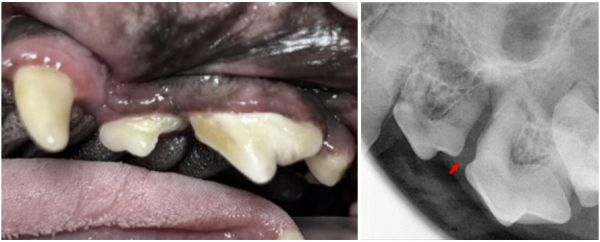

우측 어금니에서는 육안으로

치주염과 치조골 소실이 뚜렷하게 보였습니다.

방사선상 107·108·110번 치아는

· 치조골 50% 이상 소실

· furcation involvement(화살표) Class 3 이상

이 경우 강아지 치아 보존이 매우 어렵기 때문에 발치 후

봉합이 가장 안전한 선택이었습니다.